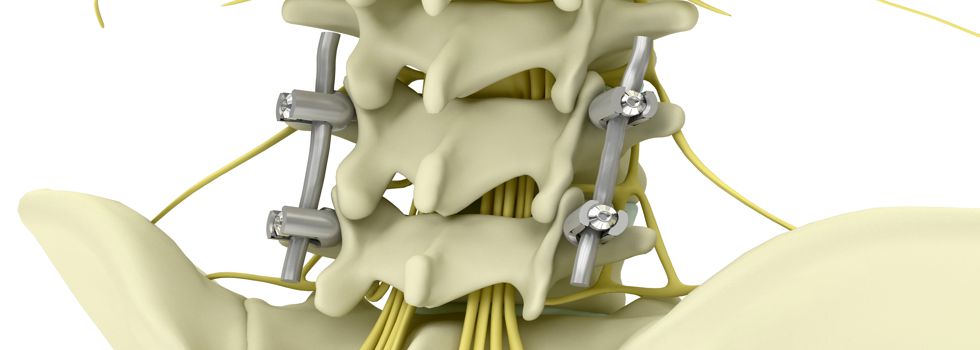

The specialisation track Endoprosthetics focusses on various medical devices and products that permanently remain within the human body and completely or partially assume the functions of the replaced body part. This especially includes knee, shoulder and hip joint endoprostheses respectively.

Graduates are enabled to professionally work in various industrial sectors including but not limited to medical engineering and engineering science. Job definitions may include the development, production and optimisation of medical implants.

Possible fields of application cover complex and comprehensive areas: research, predevelopment, development, precommissioning inspection, calculation, construction, launching as well as dimensioning, evaluation, servicing and maintenance of medical devices for an application within the human body. Besides industrial sectors, capabilities can be found at service providers (TÜV and further governmental and independent testing institutes), public certification and licensing authorities, public research institutions (Max-Planck and Fraunhofer institutes) and universities. Expert activities in a self-employed or regular employment relationship can also be part of the professional perspectives.